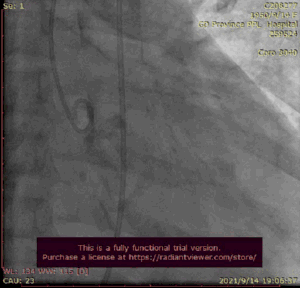

瓣膜释放

撤出大鞘心脏复跳